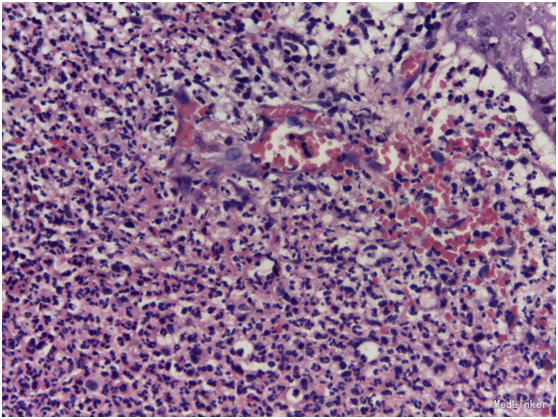

皮损:右面部可见分别4*5cm和1.5*1cm红色浸润性斑块,表面散在米粒至龙眼大小结节、脓疱。 辅助检查:初步诊断:面部皮疹性质待查:Sweet’s综合征;孢子丝菌病;淋巴瘤;其他?血常规白细胞及中性粒细胞比例升高,血沉增快;皮损分泌物镜检真菌阴性;皮肤病理:表皮局部溃破,棘细胞间海绵水肿明显,可见较多嗜中性粒细胞外渗入表皮;真皮浅层组织水肿,浅中层见大量嗜中性粒细胞浸润,其内可见破坏残留的毛囊上皮组织。符合Sweet’s综合征改变。